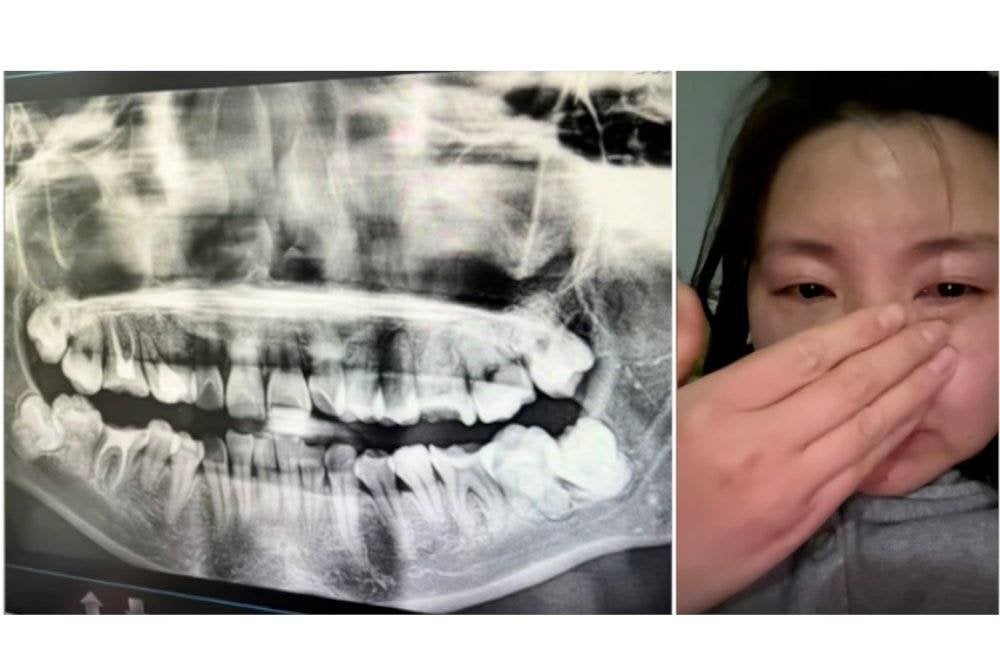

Mangsa, Wu, 34, dari wilayah Anhui, menjalani prosedur di Hospital Perbandaran Anqing pada 12 Mac lalu untuk mencabut gigi geraham bongsu.

Doktor tersilap mencabut gigi yang sihat sebelum memasukkannya semula secara paksa dan mengikatnya dengan dawai bersama beberapa gigi lain tanpa anestesia atau ubat tahan sakit.

Akibatnya, Wu mengalami kerosakan gigi, bengkak muka, tidak boleh makan dan hanya mampu minum air selama beberapa hari. Kesakitan itu juga mengganggu tidurnya.